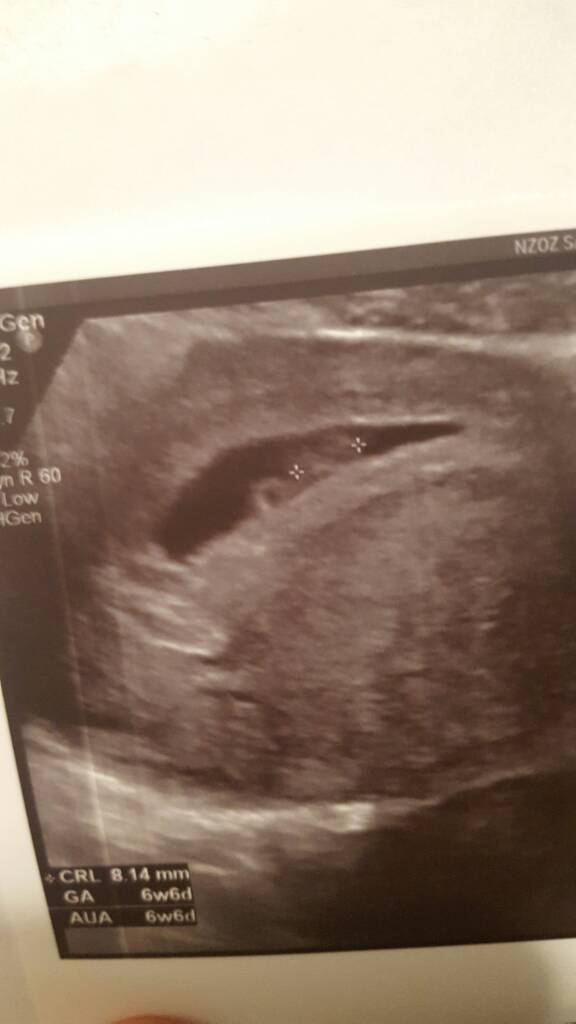

...........:::::::6tydz i 6dni:::::::::..........